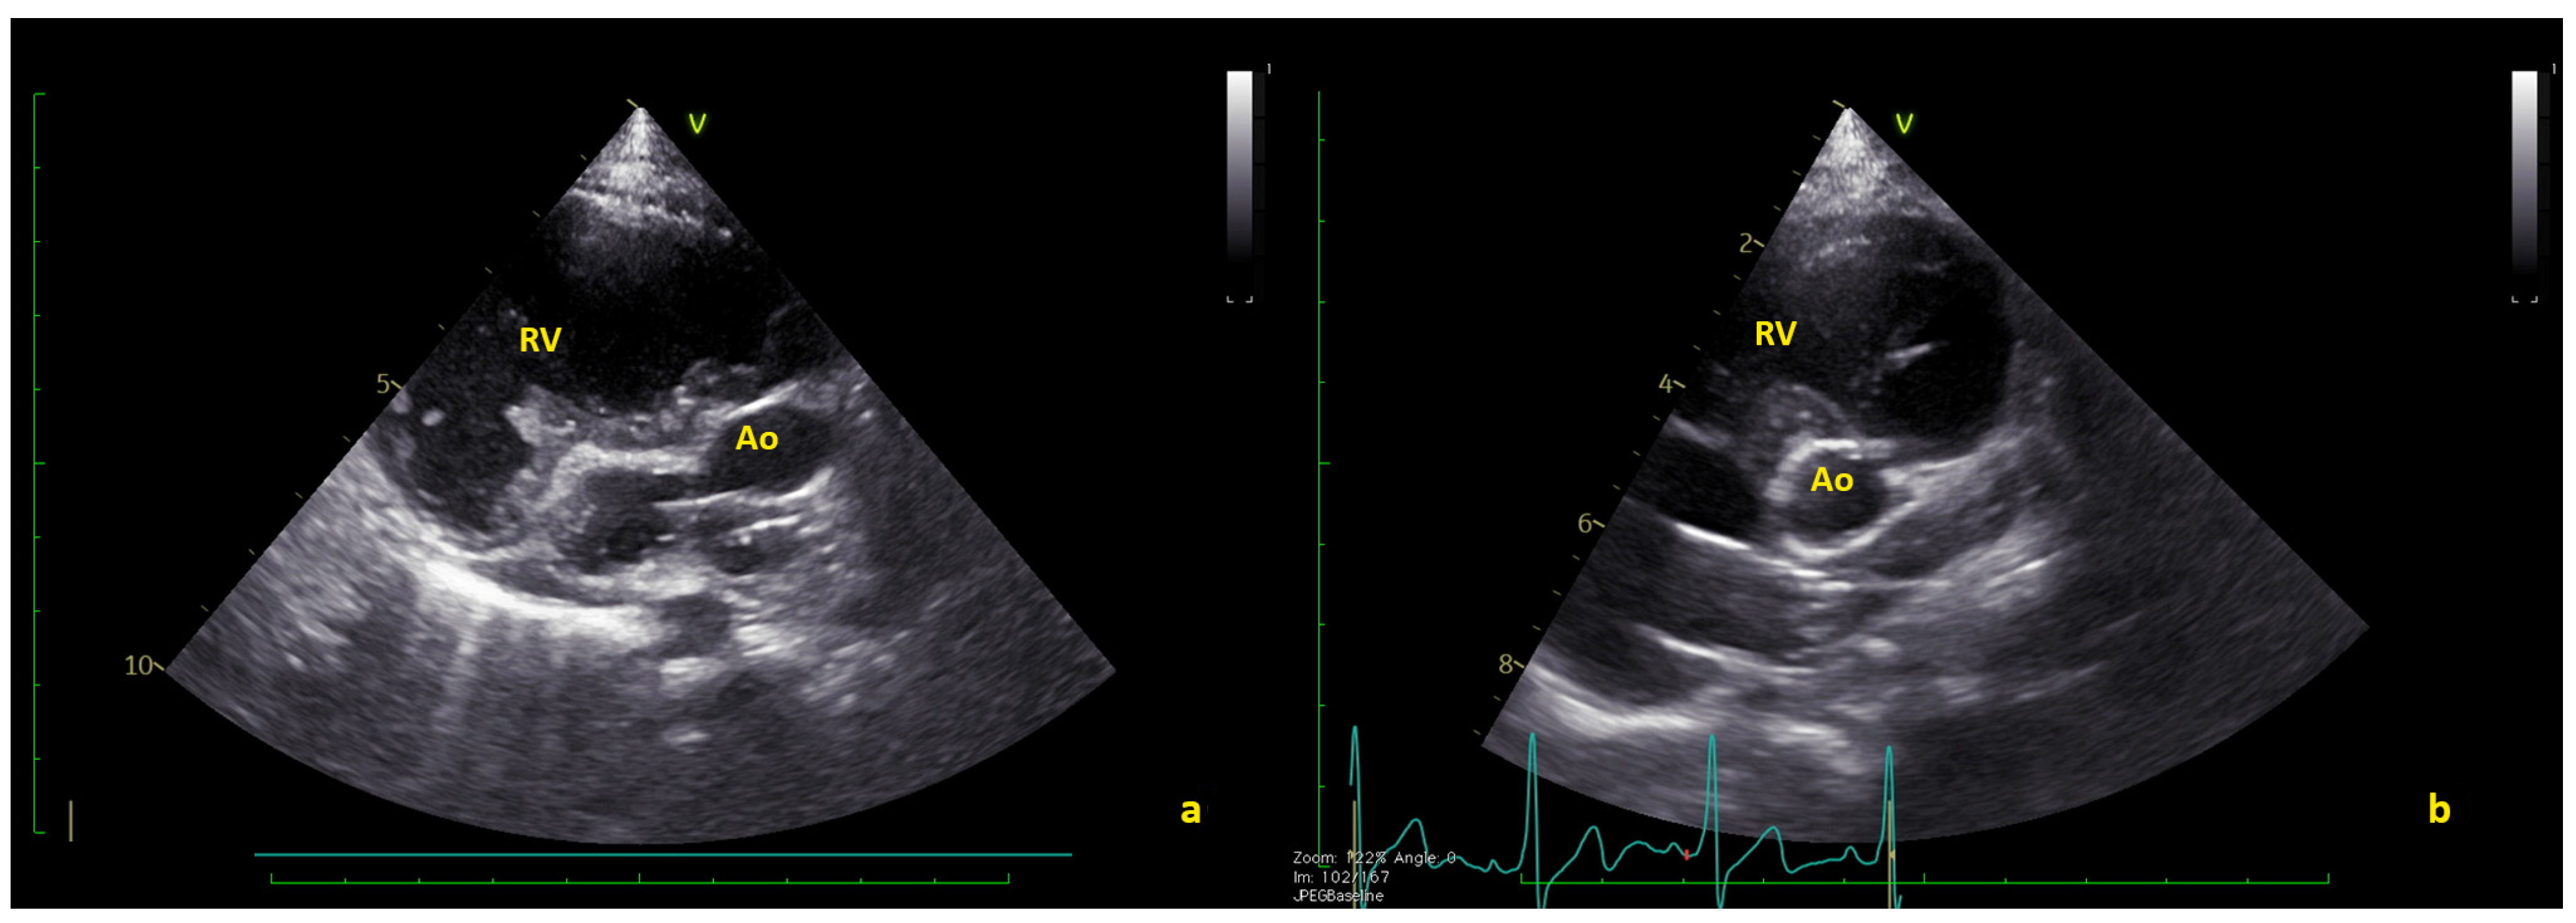

Figure 3.

(a) Long axis and (b) short axis views showing the complete thrombus resolution. Ao = native aorta; RV = right ventricle (Videos S3 and S4).